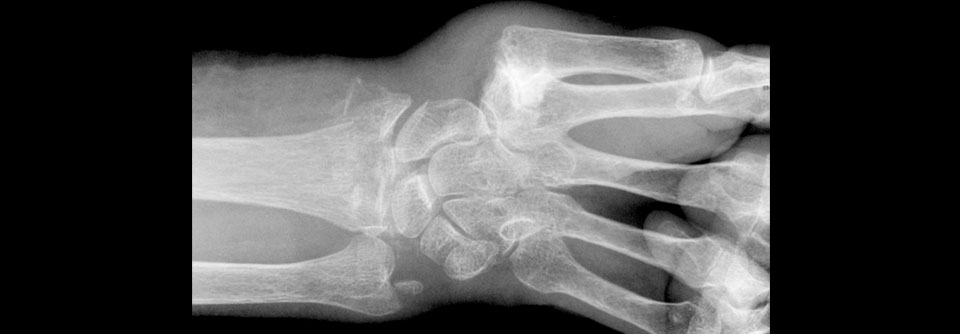

Bei Osteoporosepatienten, die knochenstärkende Medikamente bekommen, muss ein Drug Holiday sehr sorgfältig gegen das damit oftmals verbundene Frakturrisiko abgewogen werden.

Wer eine Osteoporosebehandlung abbricht oder vorübergehend aussetzt, muss mit einem erhöhten Frakturrisiko rechnen. Das geht aus einer asiatischen Bevölkerungsstudie hervor, berichtet Professor Dr. Ian Reid von der Universität Auckland in Neuseeland.

Zur pharmakologischen Therapie der Osteoporose existieren im Wesentlichen zwei medikamentöse Strategien – Bisphosphonate und der Antikörper Denosumab. Ein Forscherteam um Shau-Huai Fu aus Taiwan wertete nun die Daten von mehr als 3.000 Patienten aus, die nach einer Hüftfraktur über mindestens ein Jahr Bisphosphonate oder Denosumab erhalten hatten.